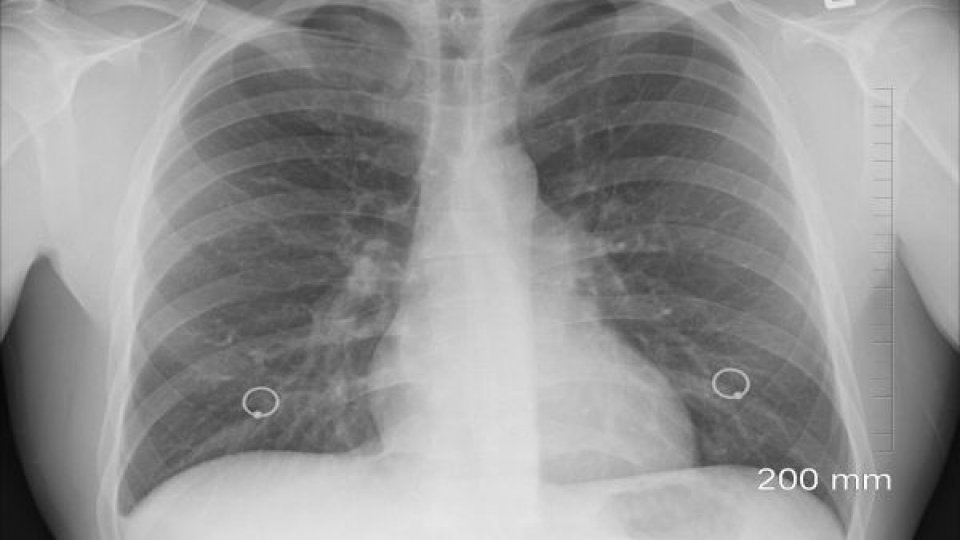

Creştere cu 37% a numărului de internări ale pacienţilor cu pneumonie

Numărul pacienţilor din judeţul Bistriţa-Năsăud diagnosticaţi cu pneumonie săptămâna trecută şi care au necesitat spitalizare a fost cu 37% mai mare decât în săptămâna precedentă, iar doi dintre aceştia, cu vârste de peste 65 de ani, au decedat, potrivit datelor publicate marţi pe site-ul Direcţiei de Sănătate Publică.

Din cele 164 de cazuri de pneumonie raportate de medici în perioada 13-19 noiembrie, 52 au presupus internarea pacienţilor, cei mai afectaţi fiind vârstnicii (63 de cazuri, cu 27 de internări).